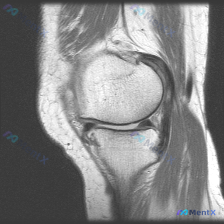

报了软骨异常却找不到病变?这张膝关节MRI给大家提个醒

这是一张膝关节MRI T1加权轴位扫描影像,核心问题是:临床提示存在「软骨异常」,需要解读影像表现并分析原因。

- 骨性结构:股骨远端滑车、髌骨的骨皮质完整,松质骨髓信号均匀,没有局灶性异常信号、骨折或者骨破坏

- 关节软骨:股骨滑车表面软骨厚度均匀,本层面没有看到局灶性缺损,髌骨后方关节软骨也没有明显变薄或者剥脱

- 髌股关节对位:髌骨和股骨滑车对合良好,没有半脱位,关节间隙正常

- 软组织:周围肌腱、脂肪没有异常肿胀或高信号,关节囊没有明显积液,滑膜也没有增厚

从这张单层面T1影像来看,没有发现明确的软骨结构性异常,和临床提示的「软骨异常」存在一定冲突,我们来一步步拆解分析。